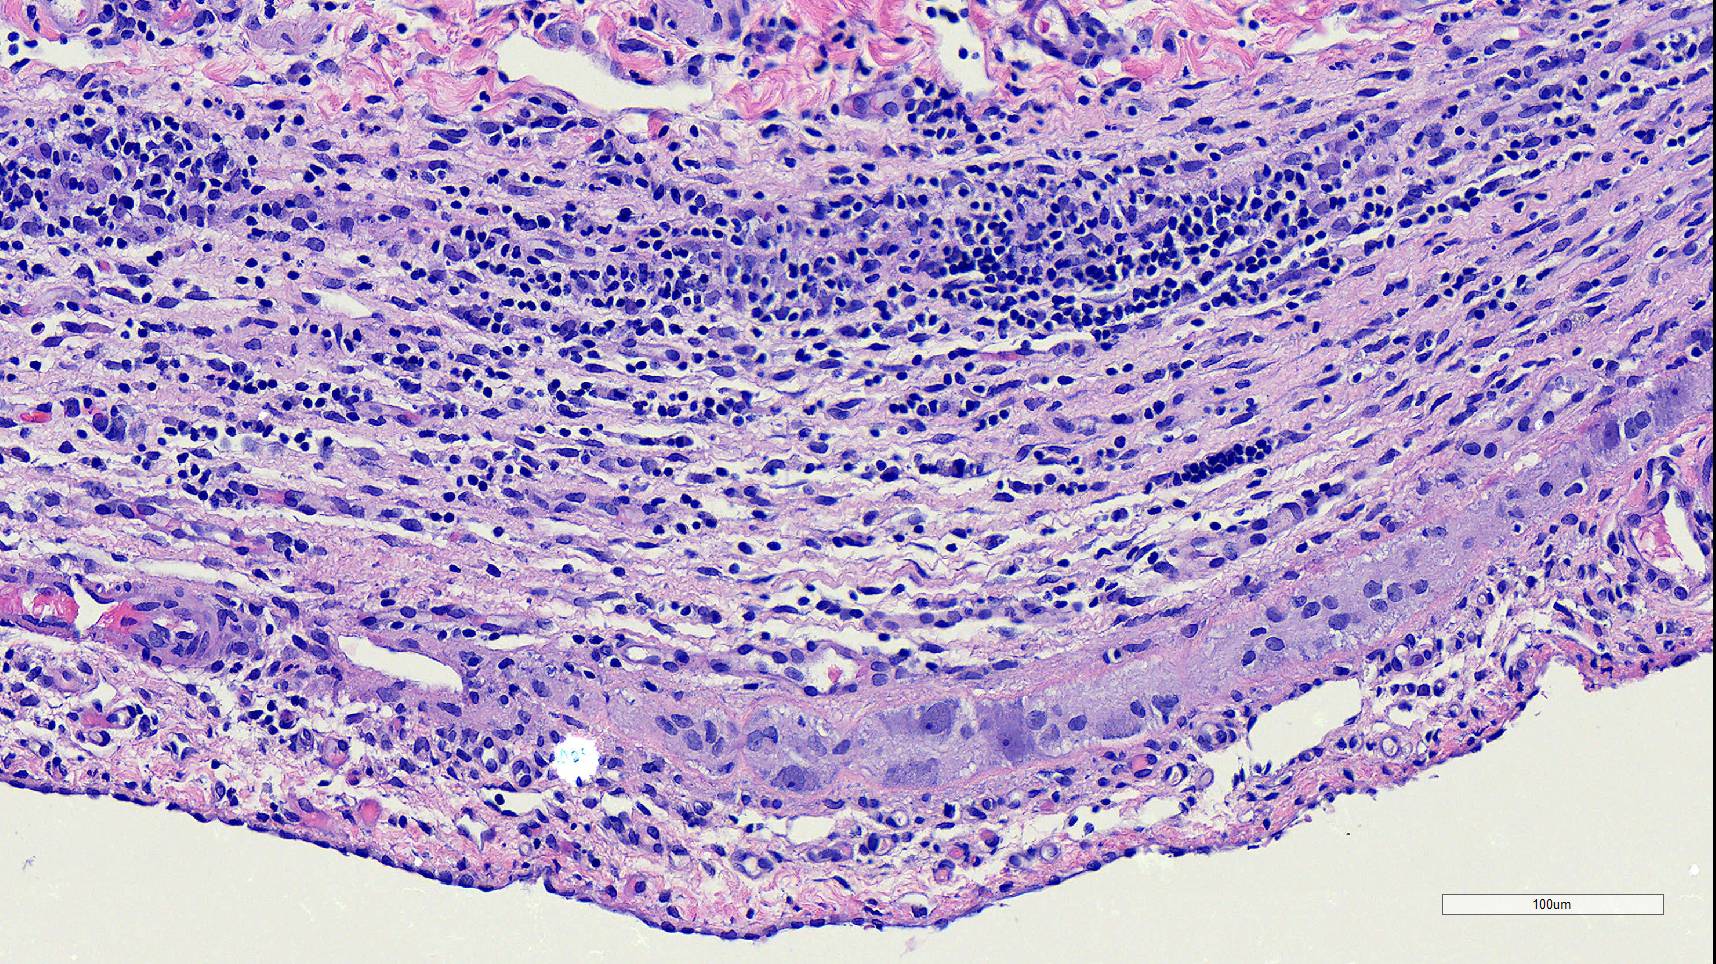

Microscopic Description:

Duodenum, jejunum and ileum: Diffusely throughout the sections, there is partial to complete loss of the leiomyocytes of the outer and inner muscularis, which are multifocally replaced by loose fibrous connective tissue (fibrosis). The remaining smooth muscle is infiltrated by large numbers small and intermediate lymphocytes, few macrophages and neutrophils. The same inflammatory infiltrate is present throughout the muscularis mucosae. Remaining leiomyocytes have pale, frequently vacuolated cytoplasm. In the submucosa, muscularis and serosa there are small to moderate numbers of perivascular lymphocytes. Small lymphocytes, and infrequently neutrophils, surround or infiltrate the myenteric and submucosal ganglia, though neurons do not exhibit degenerative changes. The lamina propria contains a markedly increased number of lymphocytes, plasma cells and a mildly increased number of eosinophils. The epithelium is diffusely overlain by myriad bacterial rods. The serosa is mildly expanded by increased clear space (edema) and is lined multifocally by markedly hypertophied mesothelium. In the stomach a similar process is observed but restricted to the outer aspect of the muscularis with a patchy/multifocal distribution and sparing of the muscularis mucosae. (section not submitted).

Duodenum, jejunum and ileum: Severe, diffuse, chronic lymphocytic leiomyositis with severe muscularis atrophy; marked, diffuse, chronic lymphoplasmacytic enteritis.

Microscopic findings reported for this condition consist of mild to marked mononuclear infiltrate, myofiber degeneration and fibroplasia or fibrosis centered within the muscularis propria of the stomach, small and large intestinal wall with the jejunum being the most severely and chronically affected segment.7,15 In early lesions the inflammation and smooth muscle degeneration are segmental, random between the outer and inner muscularis layers and sparing of the muscularis mucosae.15 Concurrent cecal involvement leading to impaction has also been described.5 Consistent histologic findings included T-lymphocyte inflammation within the muscularis propria with relative sparing of the mucosa, submucosa and neural plexuses.14 In one case report the inflammatory infiltrate was predominantly of B-lymphocytes and featured extensive angiogenesis.6 Leiomyocytes appear to be the target of the inflammation given the presence of various stages of degeneration leading to complete myofiber loss in chronic stages of the disease. Superficial inflammation is a frequent secondary finding in CIPO and has been associated with bacterial overgrowth, which were changes observed in this case.6 Neuropathy has not been a feature in most reports of canine CIPO. Inflammatory cells obscuring the myenteric and submucosal plexuses in this case were considered an extension from the neighboring inflammation as no degenerative changes were observed in the neurons. Myenteric ganglionitis has, however, been reported occurring concurrently with leiomyositis.10

Small intestine: Leiomyositis, lymphocytic, chronic, diffuse, severe, with marked smooth muscle loss and fibrosis.